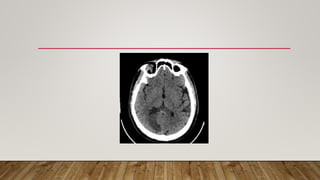

• Presentation of stroke?

• CT Brain done

COURSE CHANGE (SECOND TWIST) RADIOLOGY

27/10/2023 CT BRAIN